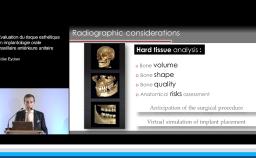

La présentation du Dr Rousseau reprend les choix auxquels est confronté le chirurgien-dentiste lors de la mise en place d’un implant dentaire.

De l’incision jusqu’aux sutures, le praticien fait face à une multitude d’options thérapeutiques qui conditionne la survie voire le succès de l’implant. La plupart des choix chirurgicaux repose sur la bonne compréhension des mécanismes biologiques de la cicatrisation et de l’homéostasie. Comprendre ces mécanismes, c’est orienter ses choix chirurgicaux vers un exercice raisonné de l’implantologie et accroître ses chances de succès.